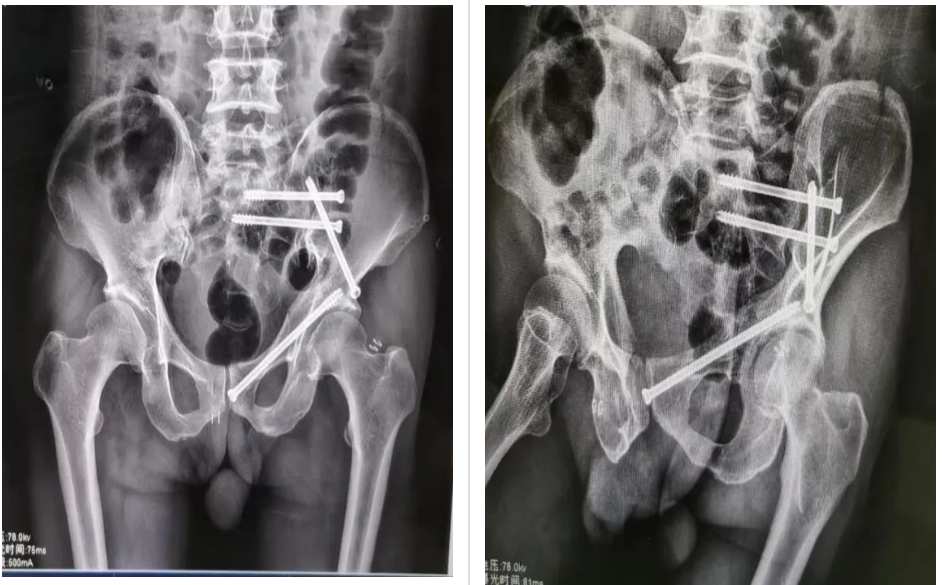

术中,在医院手术室的大力支持下,主刀医生冷明昊主任首先将定位追踪器安置在患者髂棘合适位置上,再结合CT透视所得将患者骨盆影像资料导入手术机器人中,通过机器人自动化算法将影像图片与骨盆实体情况进行精准配对,并在显示器上规划好骶髂螺钉、前柱螺钉位置、长度以及角度,随后准确无误地将骶髂螺钉、前柱螺钉植入患者体内。手术全程通过机器人监视下调整角度,快速定位、精准植入、切口仅用1cm,术中出血量约10ml,手术安全顺利结束。术后,患者恢复良好,目前可在床上自行翻身、端坐等活动。